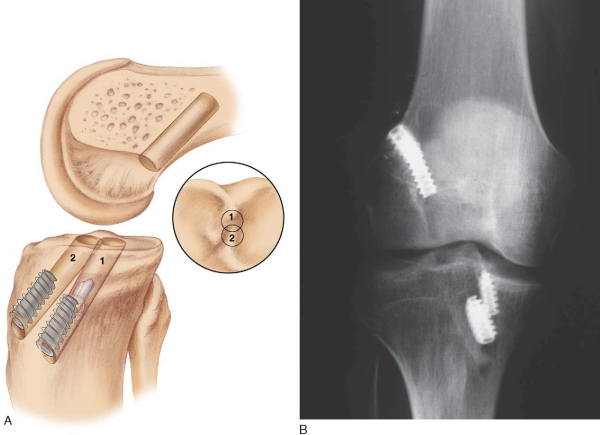

It is critical to consider whether former hardware will require removal or whether it may be bypassed at revision surgery. A variety of interference screws are commercially available with differing morphologic appearances radiographically. Most can be removed with a standard 3.5-mm screwdriver, although a screw manufactured by Instrument Makar (Okemos, Mich) requires a threaded extractor. If previous tunnels are nonanatomic and nonoverlapping, the hardware can generally be left in place (Figs. 64-3 and 64-4 [3] [4]). If the tunnels will overlap, the hardware may require initial removal for the new tunnel to be made, but it may have to be subsequently reinserted to provide construct fixation stability. In our experience, bioabsorbable screws are generally not resorbed at the time of revision surgery and frequently fracture on attempted removal secondary to softening. The surgeon may therefore have to ream through these screws to properly position the new tunnel.

The ideal location for the femoral tunnel is in the 1-o’clock (left knees) or 11-o’clock (right knees) position with 1 to 2 mm of intact posterior wall. Careful inspection of the previous tunnel is performed; if it is in the correct location, it can be reused. However, if it is positioned too anterior, a new tunnel is drilled behind it (see

Fig. 64-3A

). In this case, we recommend keeping the old hardware in place to act as an anterior buttress. On occasion, a deficient posterior wall precludes interference screw fixation with the endoscopic technique, in which case a two-incision technique can be used to secure the ACL on the anterior femur instead.